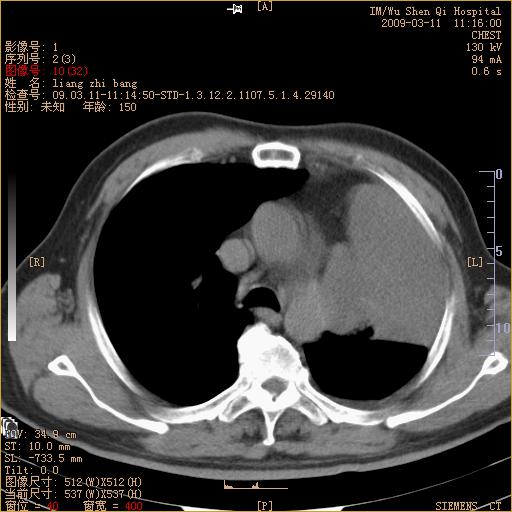

标题: CT18604:男,60岁,咳嗽一月余 [打印本页]

标题: CT18604:男,60岁,咳嗽一月余

1)考虑左肺上叶中央型肺癌并左肺上叶肺不张;建议必要时行纤支镜检查进一步明确诊断。2)左侧胸腔积液。

肺门肿块、支气管开口闭塞伴肺不张及胸水!典型的中心型肺癌变现!

1、左肺上叶中央型肺癌并上叶阻塞性肺不张。

2、左侧胸腔少量积液,右侧胸膜轻度增厚。